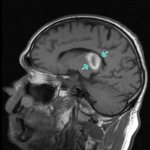

Dysarthria is a disorder of speech skills due to damage to the speech motor system. The localization of the pathological process leading to the problem can develop at different levels of the nervous system responsible for the formation of sounds and the logical order of the story:

• nuclei of the cranial nerves responsible for the nervous control of the tongue, lips, soft palate, etc.;

• pathways between the cortex and cerebral nuclei;

• subcortical centers;

• the cerebellum and pathways, pathways from and to it;

• cerebral cortex.